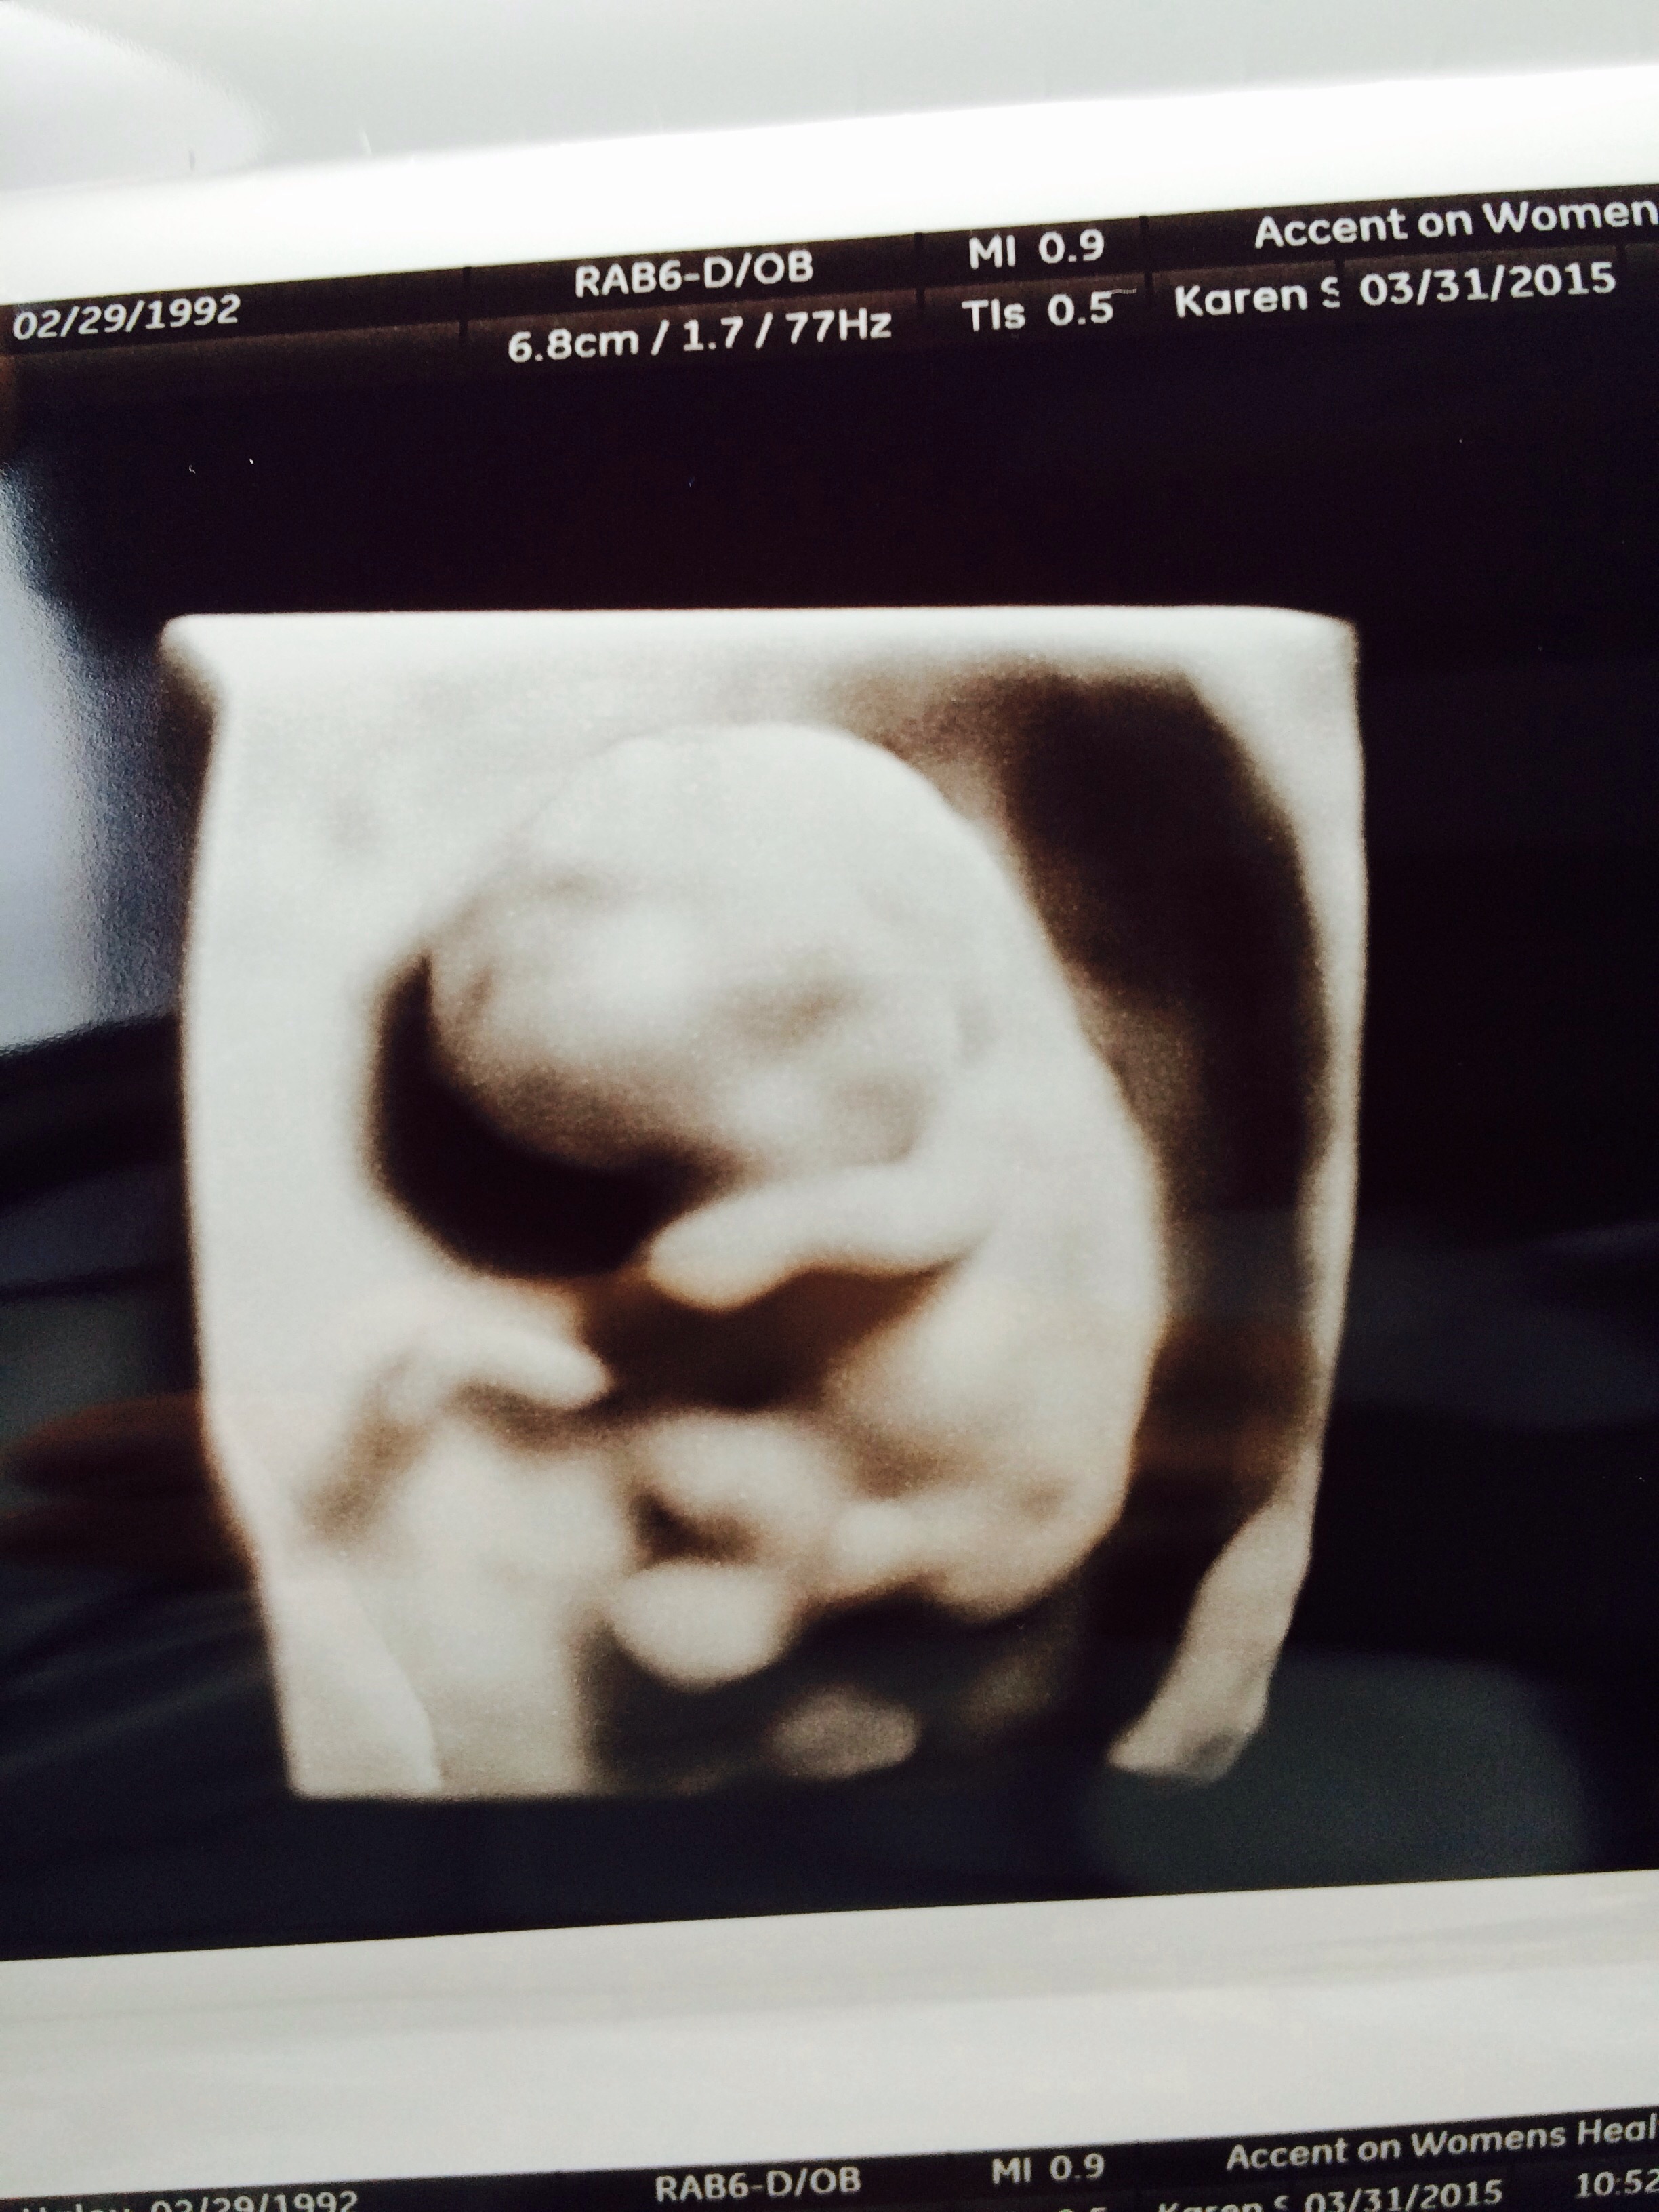

Got a surprise ultrasound today at 14w1d- thought we were just going to hear the heartbeat but we got pics too! Last time was at 9 weeks and she looked like a white smear on the U/S. Now look! So exciting!!